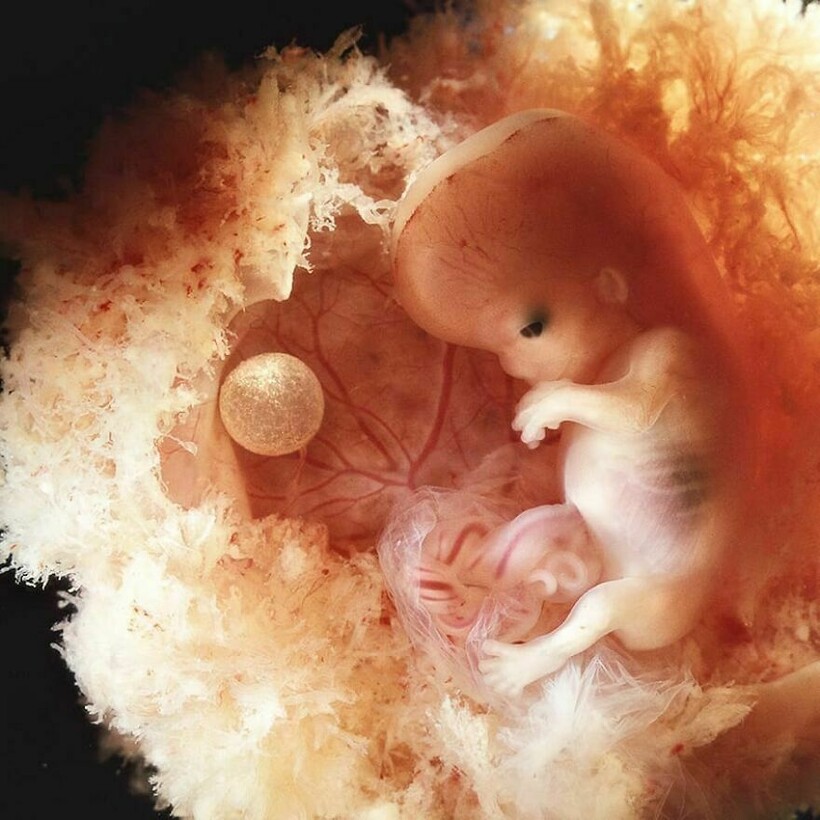

Леннарт Нильссон стал настоящей легендой фотографии, ведь он сделал то, чего не удавалось никому: показал миру, как развивается ребенок в утробе матери. Его проект «Ребенок родился» был создан в 1960-х годах, и он представляет собой детальные снимки эмбрионов на разных стадиях развития. Фотографии стали сенсационными, впервые они появились в журнале LIFE, и одна из них украсила обложку. На протяжении многих лет эти снимки публиковали в разных журналах.

Фотограф снимал детей в утробе матерей во время медицинских процедур

Он присутствовал на амниоцентезе и лапароскопии

Нильссон не скрывал, что снимал и эмбрионы после выкидышей и абортов

Снимки стали сенсацией, их много раз перепечатывали, они и сегодня вызывают отклик у зрителей

Его фото позволили заглянуть в чудо рождения, они стали источником знаний и вдохновения